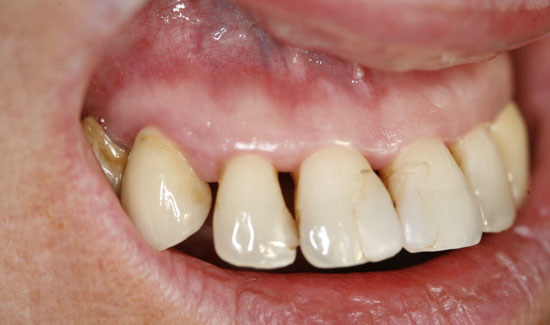

We are reporting on the successful treatment of an advanced case of Parodontitis marginalis profunda in the frontal area of the upper jaw of a 42-year old female patient with local application of ozone gas with the Prozone of W&H. Svea Baumgarten, Dr. med. dent., M Sc, accredited implantologist shares her experiences with ozone treatment.

The patient introduced herself at our practice, inquiring about preserving the front teeth of her upper jaw, which were suffering from chronic periodontitis. We discovered general formation of pockets

(> 10 mm), spontaneous bleeding and a degree of tooth mobility of 2/3, i.e. the teeth were candidates to be extracted. As an interim solution (it was a public holiday) until restoration could take place, we offered local ozone gas treatment.

Fig. 1: Orthopantomogram